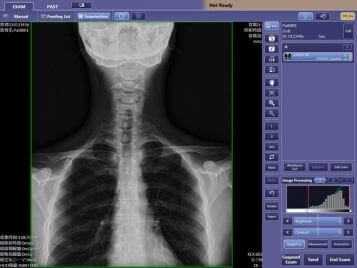

Наше оборудование.

Наша клиника оснащена современным рентген дигностическим комплексом

«Radspeed» производства фирмы

SHIMADZU , Япония.

Фирма SHIMADZU является пионером в разработке и производстве рентгеновского оборудования. Первые рентгеновские аппараты были производства этой фирмы. Одной из первых началась разработка и выпуск цифрового диагностического рентгеновского оборудования. Большое внимание компания уделяет разработке программного обеспечения, за счет которого добилась значительного снижения лучевой нагрузки на пациента при проведении исследований. Оборудование сертифицировано, соответствует современным требованиям и обладает всеми преимуществами цифровой рентгенографии.